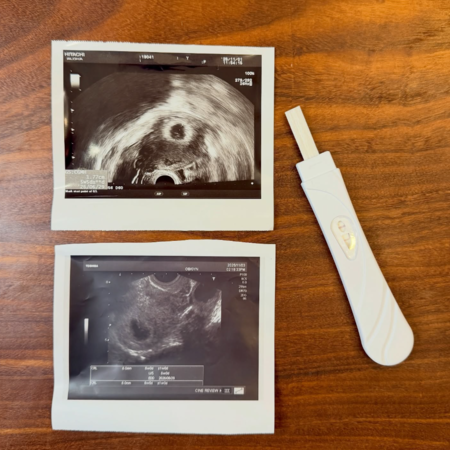

▲金老佛爺拍下超音波照和驗孕棒,記錄懷中寶寶。(圖/翻攝自Instagram/kimlafayette)